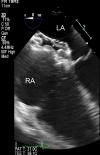

This review article will guide the reader through the basics of echocardiographic assessment of congenital left to right shunts in both paediatric and adult age groups. After reading this article, the reader will understand the pathology and clinical presentation of atrial septal defects (ASDs), ventricular septal defects (VSDs), atrioventricular septal defects (AVSDs) and patent arterial duct. Echocardiography is the mainstay in diagnosis and follow-up assessment of patients with congenital heart disease. This article will therefore describe the echocardiographic appearances of each lesion, and point the reader towards specific features to look for echocardiographically.